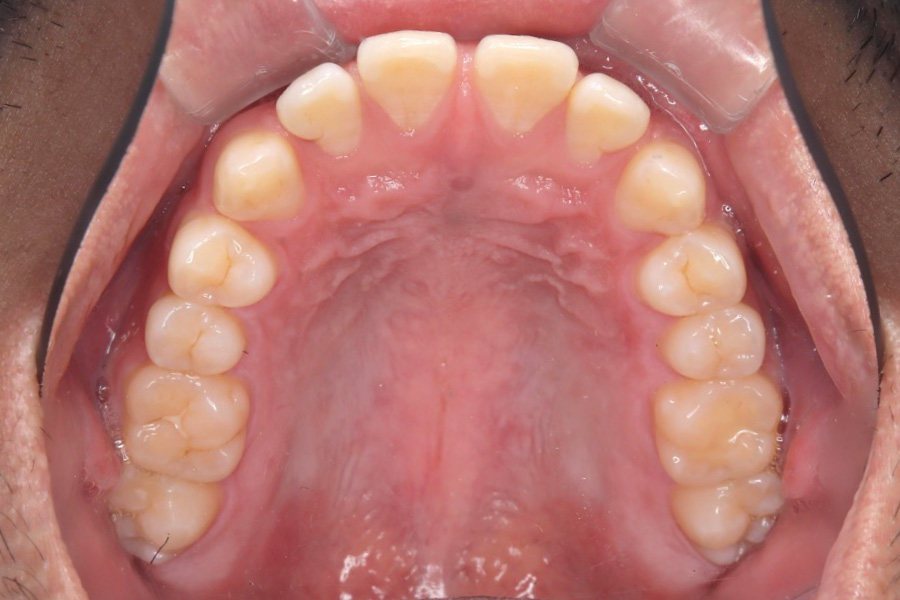

【20代男性】

歯の隙間を

インビザライン矯正で治療したケース

治療前

主訴 歯の隙間が気になる

治療内容 インビザライン矯正

非抜歯